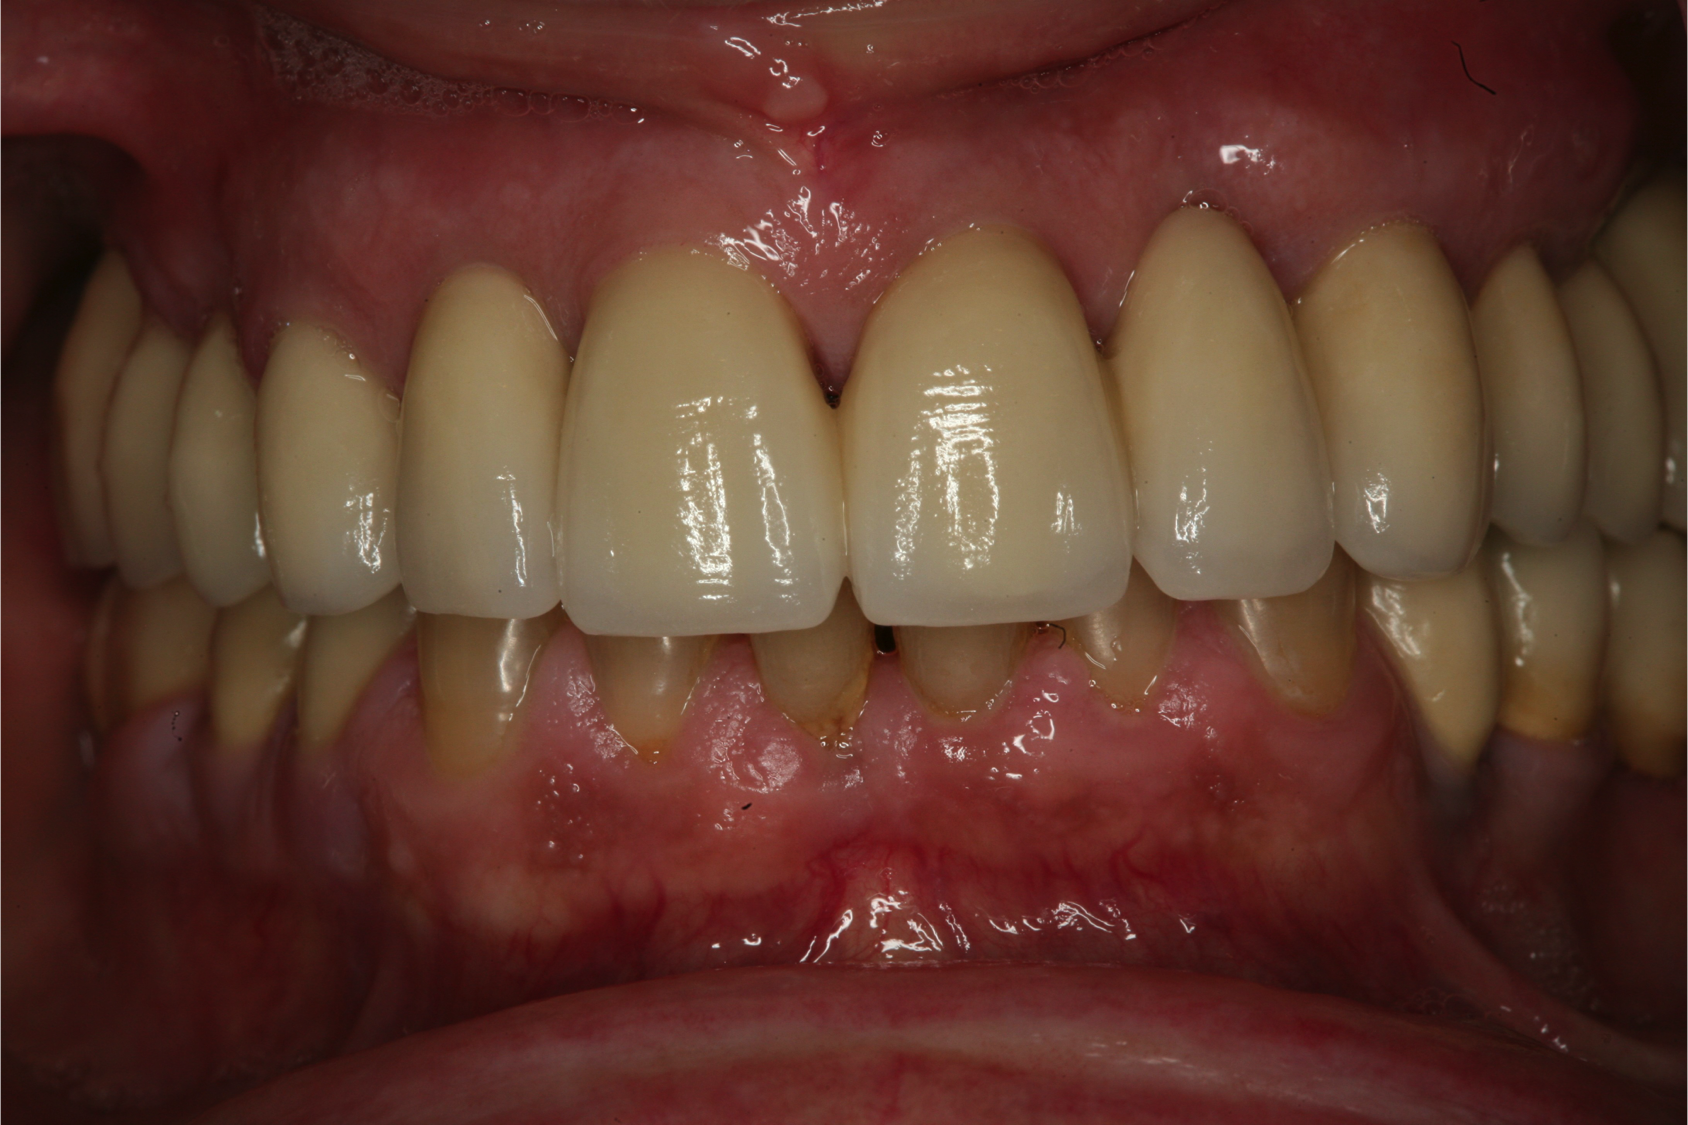

Fig 12. Frontal view (Fig 12) and occlusal view (Fig 13) of clinical application of dual-axis principles. (Images courtesy of Costa Nicolopoulos, BDS)

Fig 13. Frontal view (Fig 12) and occlusal view (Fig 13) of clinical application of dual-axis principles. (Images courtesy of Costa Nicolopoulos, BDS)